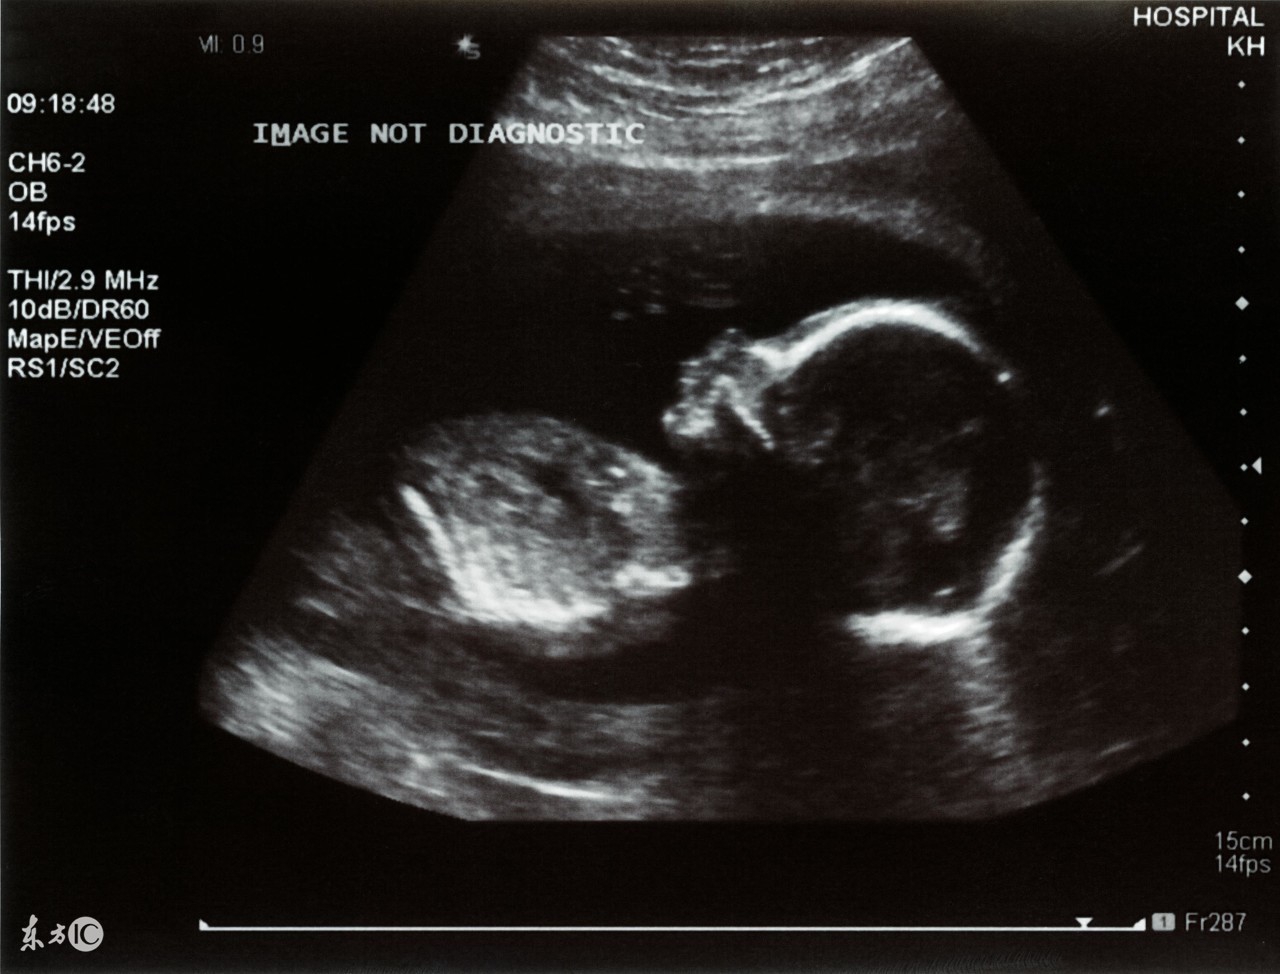

1、普通B超:也有人称为“黑白超声”,医学上称为二维超声、黑白色;

图片来源于百度图片